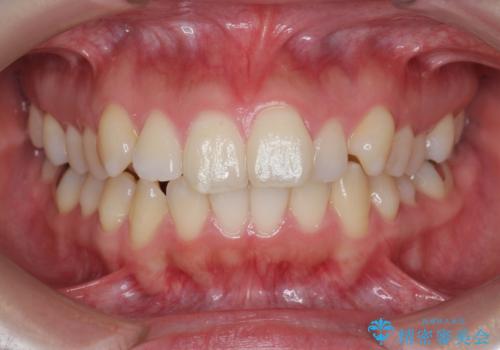

- 前歯の角度の改善を求めて矯正治療を希望し来院されました。

上下の歯は、上顎の歯が相対的に前に位置する咬合関係で押し出されるように前歯に角度がついている状態です。

咬合関係の改善、前歯の角度、がたつきを改善するため、マイクロインプラントを用いて上顎の奥歯を後方へ移動させていきます。